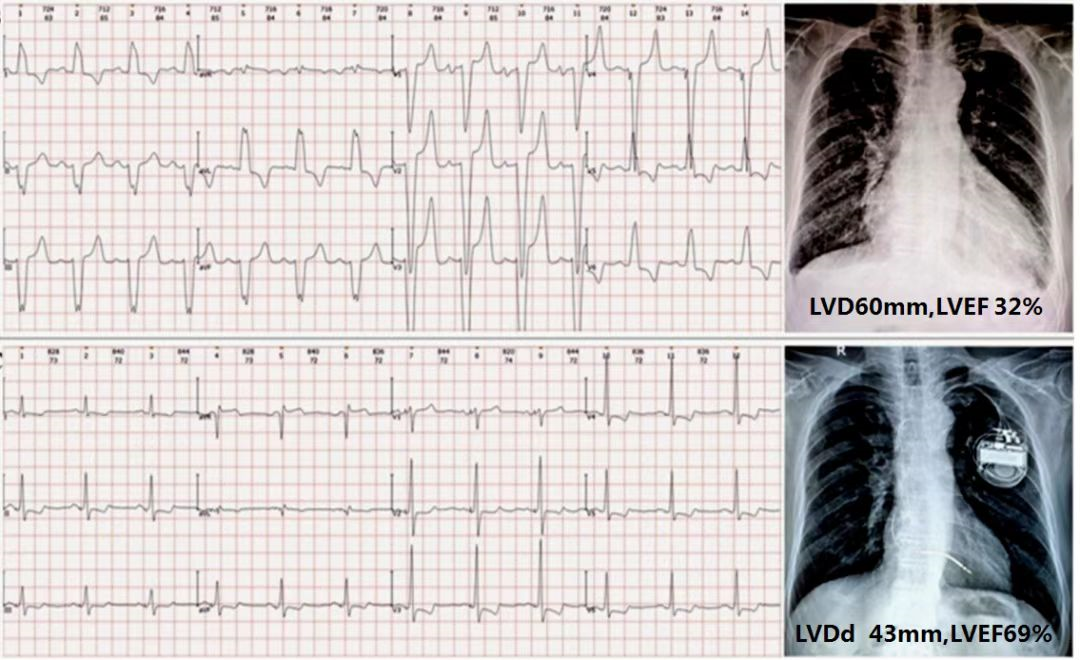

左束支起搏三月后心脏恢复正常